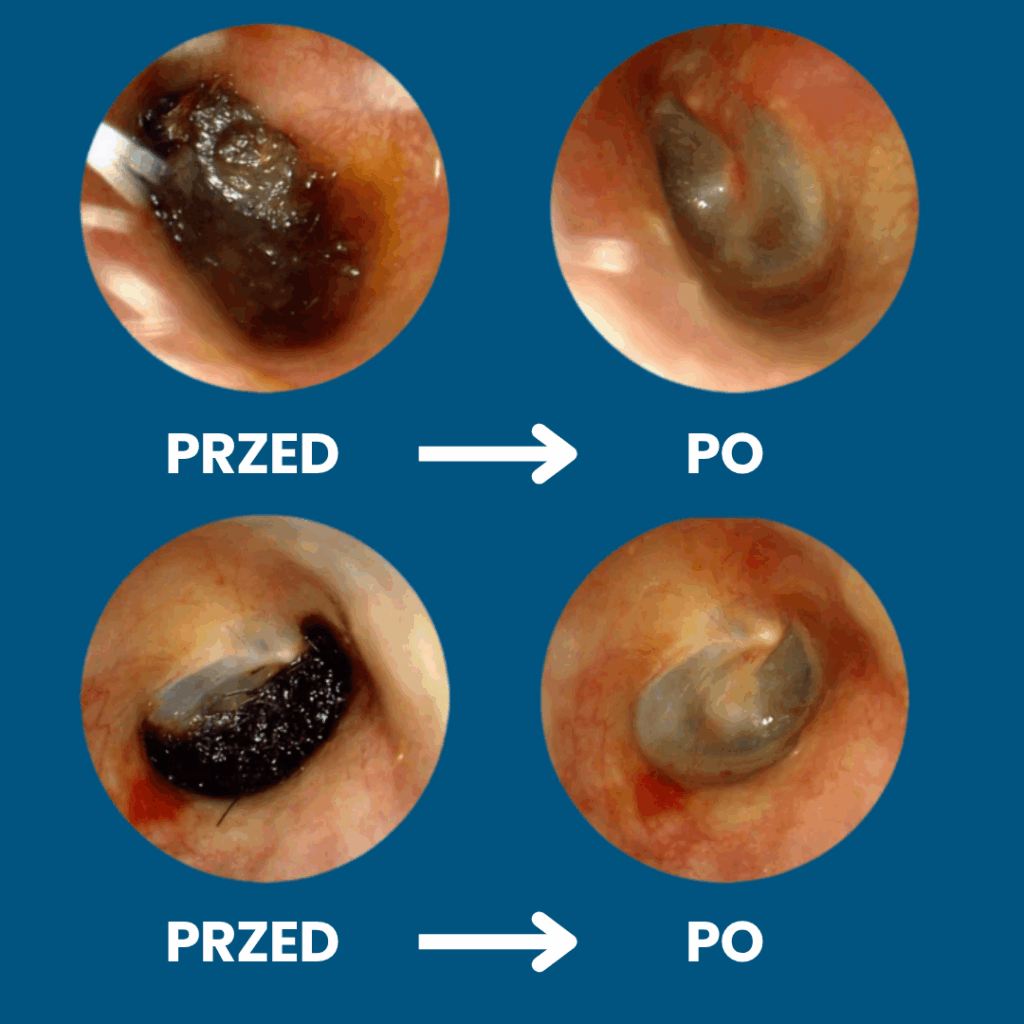

✅ Usuwa zalegającą woskowinę – nie wpycha jej głębiej jak tradycyjne patyczki

Koniec z ryzykiem urazów i infekcji — patyczki często powodują podrażnienia, infekcje i perforację błony bębenkowej. Pełna kontrola dzięki obrazowi HD 1080p — widzisz woskowinę i swobodnie ją usuwasz, zamiast ją wpychać.

Pełna kontrola dzięki obrazowi HD 1080p — widzisz woskowinę i swobodnie ją usuwasz, zamiast ją wpychać. Miękkie silikonowe końcówki zamiast patyczków — precyzyjnie usuwa woskowinę, bez ryzyka zarysowań i dyskomfortu

Higieniczne i oszczędne — wielorazowe końcówki redukują odpady i koszty wymiennych patyczków. Szybka ulga — natychmiastowy efekt komfortu i czystości uszu bez wizyt u specjalisty.

Szybka ulga — natychmiastowy efekt komfortu i czystości uszu bez wizyt u specjalisty.